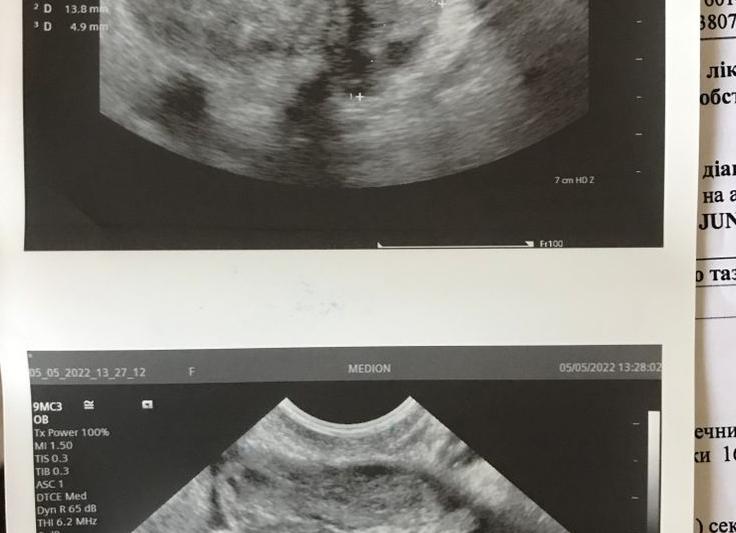

Гипоэхогенное образование в матке («гипо» – пониженный, нижний) – это участок ткани с меньшей эхогенностью, чем остальные ткани матки.

В этом месте ультразвук движется медленнее, врач видит это на экране как затемнение. Чаще всего такой структурой обладают сосудистые образования, наполненные жидкостями, то есть таким образованием может быть киста или опухоль. Однако специалист УЗИ не напишет в бланке «киста», так как для более точной постановки диагноза необходимо дальнейшее обследование, такое как биопсия.

Если врач заметил на экране темное образование, которое он определяет, как гипоэхогенное образование, он должен подробно описать этот участок: его размеры, контуры. Все это поможет гинекологу определиться с диагнозом и назначить лечение. Стоит помнить, что гипоэхогенное образование – это не всегда приговор и страшный диагноз. УЗИ имеет свои погрешности и недостатки.

При проведении ультразвукового анализа матки у некоторых выявляют гипоэхогенные включения. Это означает, что на определенном участке ультразвуковые волны движутся медленнее, выявленные образования характеризуются пониженной акустической плотностью. На экране этот участок будет визуализироваться в виде затемнения. Узлы с пониженной эхогенностью могут быть серыми, темно-серыми либо практически черными.